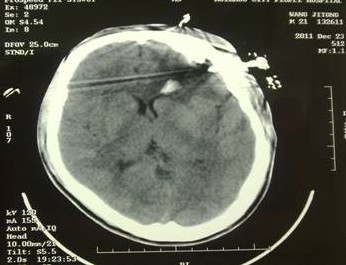

于是家屬慕名求助于我院余永強(qiáng)主任,在傷后第三天轉(zhuǎn)來我院。余永強(qiáng)主任主持術(shù)前討論,決定為患者施行微創(chuàng)手術(shù)清除血腫。通過CT掃描進(jìn)行術(shù)前精確定位,隨后在局麻下進(jìn)行微創(chuàng)手術(shù)。術(shù)中利用余主任設(shè)計(jì)研制的“e形微創(chuàng)手術(shù)定向儀”作引導(dǎo),將穿刺針準(zhǔn)確無誤置入血腫靶心,順利地清除了絕大部分血腫。術(shù)后復(fù)查頭顱CT,血腫清除超過90%(圖2)。憑借微創(chuàng)技術(shù),頭皮僅僅只需要一個(gè)直徑3毫米的小孔,通過一根高科技微創(chuàng)穿刺針,便可達(dá)到同樣的甚至更好的治療效果(圖3)。術(shù)后留置引流1天,第7天即痊愈出院。手術(shù)達(dá)到近乎“完美”的效果!患者親屬大為感慨微創(chuàng)手術(shù)的“神奇”,術(shù)后專程送來錦旗一幅――“微創(chuàng)手術(shù)顯神功” !(圖4)

圖2(1):術(shù)后立即復(fù)查CT,血腫清除90%以上,穿刺針定位精確,

無損傷出血;